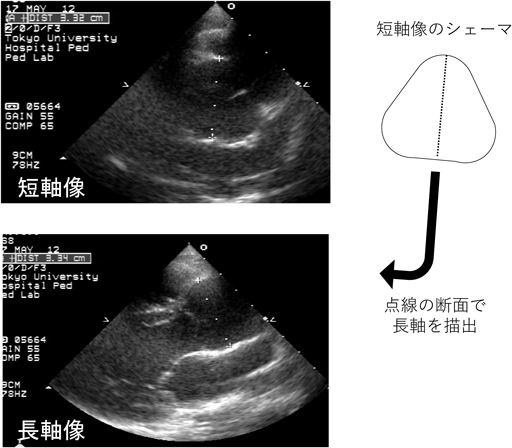

Marfan症候群の診断および治療方針の決定には,心臓超音波を用いた大動脈基部拡張の評価が重要である.Valsalva洞径のZ value≥2を大動脈基部拡張ありと判断するが,改訂ゲント基準においては,Z value≥3が家族歴のある小児における基準になっていることに注意する.小児においては,成長に伴い大動脈基部径の絶対値が増加することが想定されるため,経時的変化はZ valueで比較する.小児においては様々なValsalva洞径のZ valueの計測方法・計算式がある.改訂ゲント基準でも,米国マルファン財団のホームページに記載されている収縮期のInner-edge法やRomanらの報告にある拡張期のLeading edge法の両方が記載されているが,当院では後者を用いている(Fig. 47).診断だけでなく治療適応を検討する際にも,Romanらと同様の方法で大動脈基部径を計測するのが一般的だが,この方法は験者間のばらつきが比較的大きい方法であるため,特に経時的変化を評価する際には注意が必要である.Fig. 5に示すように,多くのMarfan症候群の患者において,大動脈基部の短軸像は円形というより三角形に近い形状をしている.そのため筆者は,短軸像で三角形の高さにあたる部分の距離を計測した後に,その短軸で計測した方向の断面を長軸で描出し,大動脈基部径の計測を行っている.正しい断面の描出ができている場合は,短軸と長軸の計測径は一致し,再現性高く大動脈基部の径を評価することができる.Romanらの報告のように,心室の長軸にあわせて大動脈基部を描出した場合,Fig. 4のシェーマにあるようにValsalva洞は胸壁側も背側も膨らんで見えるが,Fig. 5の方法では背側のValsalva洞はほぼ直線状に描出される.小児のMarfan症候群で,経時的変化を評価する際は,再現性の高いFig. 5の方法が有用である.小児期に大動脈弁閉鎖不全を認めることはまれであるが,特に基部拡張が進行した例では注意する.最終的に手術適応を評価する際は,造影CTで動脈瘤の大きさの評価を行うが,その際は動脈瘤の最大短径の計測を行う8)

Fig. 5 小児における大動脈基部評価の工夫